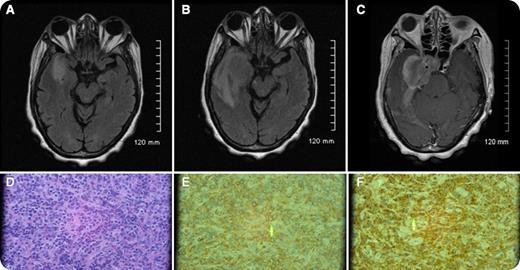

A 65-year-old woman initially presented with chronic extreme headaches. Initial magnetic resonance imaging (MRI) scans (panel A) revealed abnormal signaling possibly representing dural inflammation or a meningioma. A complete blood count at that time was within normal limits. Four weeks later, her symptoms included progressively worsening, right temporal throbbing headaches with associated right eye visual disturbance and right facial paresthesias. Repeat MRI (panels B and C) revealed enlargement of the dural mass now extending into the right cavernous sinus and right optic canal. Initial cerebrospinal fluid studies were negative for cytology and infection. A biopsy revealed a myeloid sarcoma (panels D-F). A peripheral smear revealed 10% circulating blasts, and a subsequent bone marrow biopsy revealed acute myeloid leukemia (AML) with 8:21 translocation.

In patients with AML, less than 1% present initially with prominent extramedullary disease, including myeloid sarcoma. Myeloid sarcoma may present simultaneously with bone marrow disease, precede bone marrow disease, or be seen in disease relapse. The presence of a myeloid sarcoma is diagnostic of AML independent of the blast count. Myeloid sarcoma may be found in many isolated sites, including the dura, periosteum, and bone. Myeloid sarcoma must be considered in the differential diagnosis in the presence of a rapidly progressing dural mass.